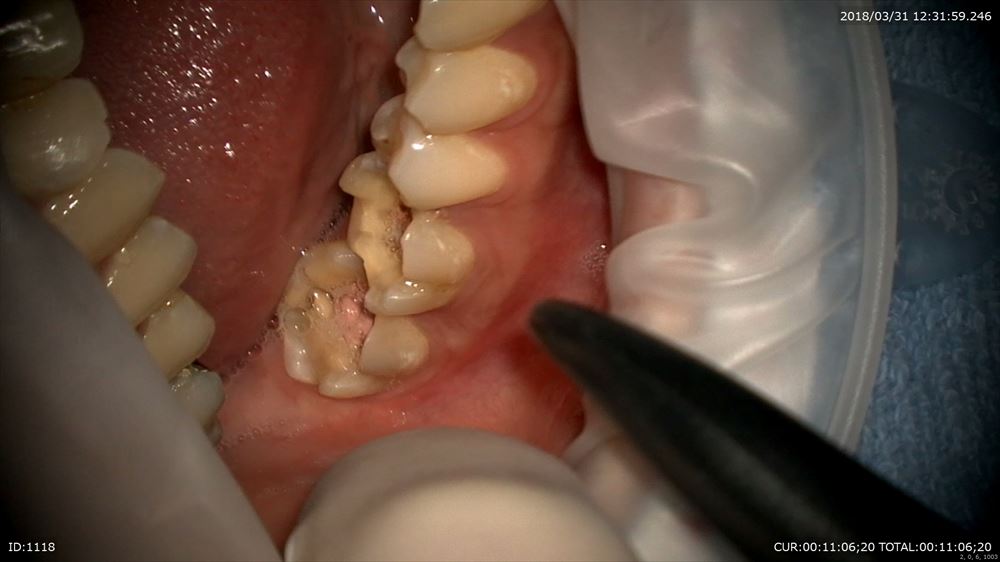

今日

症状も腫れもなく本人笑顔!!!比較写真

この様に当院では保存治療を専門に治療を行っております。

保存治療のスペシャリストとして来年度も精進して参ります。